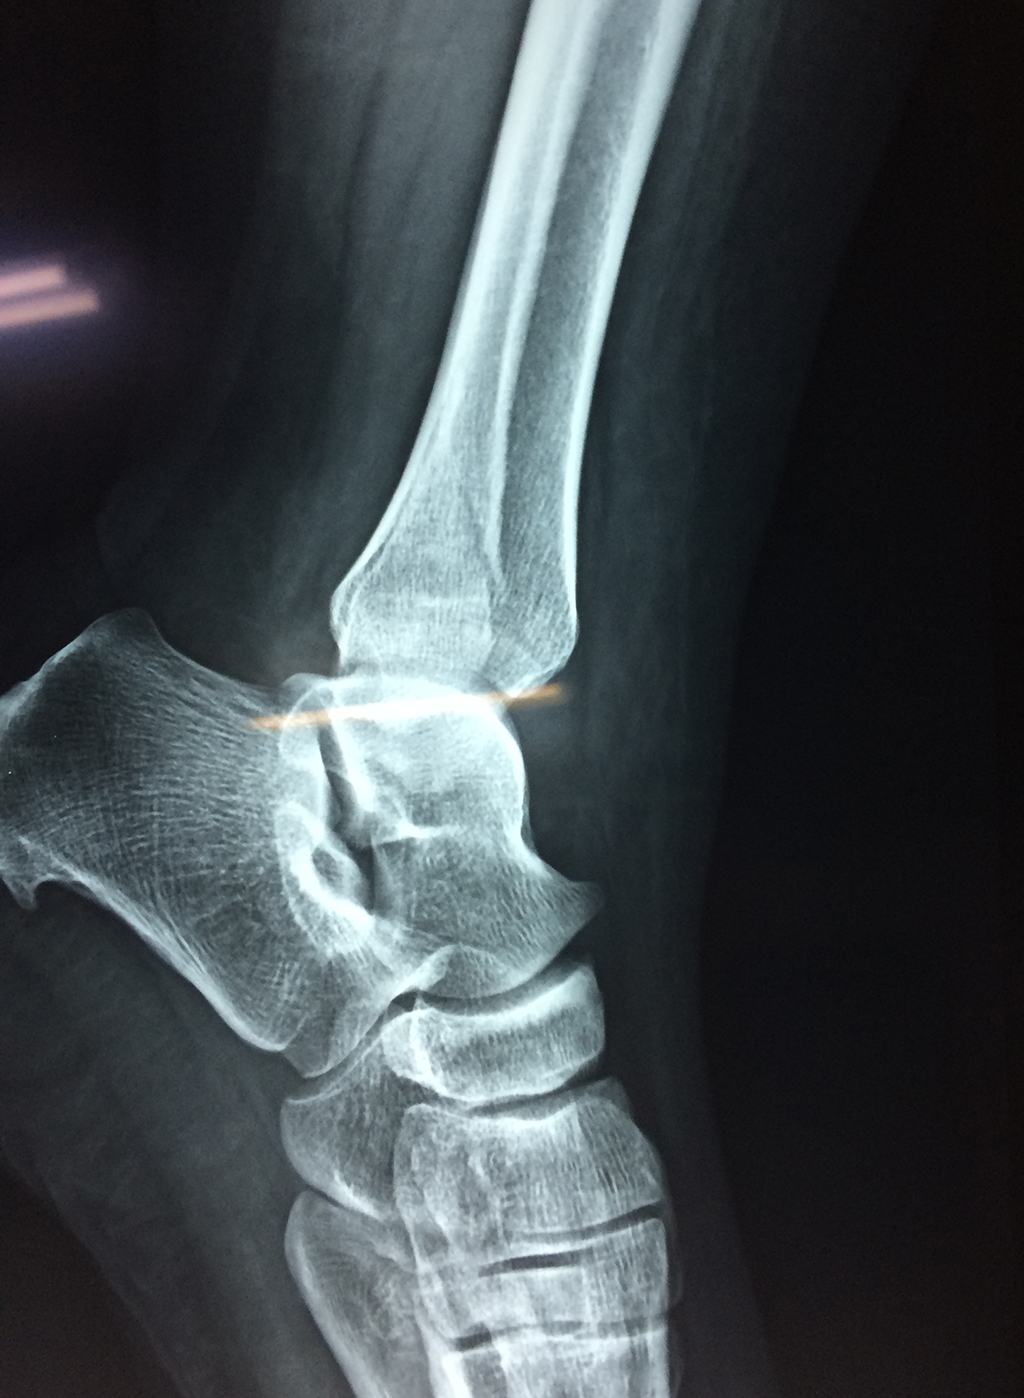

Una fractura de tobillo es la rotura de uno o más de los huesos del tobillo. Estas fracturas pueden ser:

- Parciales (el hueso está sólo parcialmente fisurado, no del todo).

- Completas (el hueso está perforado y está en 2 partes).

- Producirse en uno o ambos lados del tobillo.

Algunas fracturas de tobillo pueden requerir cirugía si:

- Los extremos de los huesos están desalineados entre sí (desplazados).

- La fractura se extiende hasta la articulación del tobillo (fractura intra-articular).

- Los tendones o ligamentos (tejidos que sujetan los músculos y los huesos entre sí) están rotos.